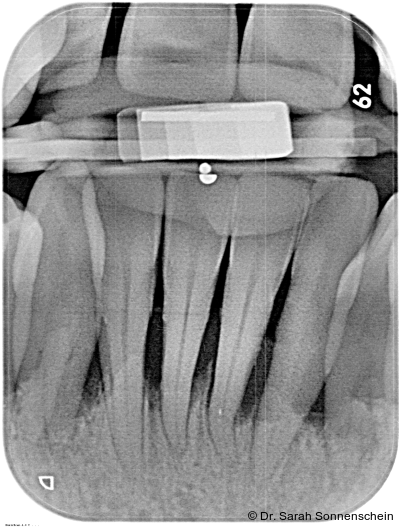

Die Abbildungen 2a–d zeigen die Eingangssituation einer allgemeinmedizinisch gesunden 37-jährigen Nichtraucherin mit Parodontitis Stadium IV Grad C, Falltyp 1 (damalige Diagnose: generalisierte aggressive Parodontitis). Ihr Hauptanliegen war der Zahnerhalt und die Beseitigung der „lockeren“ Zähne. Die Sondierungstiefen lagen generalisiert zwischen 5 und 9 mm. Die AV bei bis zu 12 mm. Die Zähne 33-43 wiesen alle einen Lockerungsgrad III auf. Auch die Oberkieferfront wies einen Lockerungsgrad II auf. Nach der Mundhygienephase erfolgte eine Full-Mouth-Disinfection mit adjuvanter Antibiotikagabe. Die Schienung der Zähne 33-43 erfolgte mittels glasfaserverstärkter Kompositverblockung. Bei Befundevaluation zeigten sich nur noch vereinzelte Taschen von bis zu 5 mm, welche reinstrumentiert wurden. Die Patientin konnte entsprechend in die engmaschige UPT (dreimonatiges Intervall) überführt werden. Zur Verbesserung der Ästhetik und Stabilisierung der gelockerten Oberkieferfrontzähne erfolgte nach Abschluss der aktiven Behandlungsphase ebenfalls eine Verblockung der Oberkieferfrontzähne und Zahnumformung im direkten Verfahren mittels Komposit. Abbildungen 3a–d zeigen die Situation der Patientin zweieinhalb Jahre nach Erstbefundung.